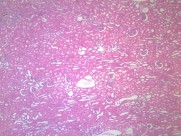

肾小管水肿(11)张

肾小管renal tubule 与肾小囊壁层相连的一条细长上皮性小管,具有重吸收(reabsorption)和排泌作用(secretion).肾小管按不同的形态结构,分布位置和功能分成三部分;近端小管,细段和远端小管。肾小管在肾髓质中。